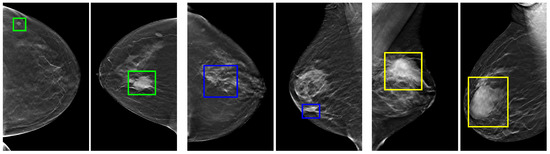

Notably, the CAD systems discussed above have made significant efforts to address the issue of breast tumor detection within DBT images, and several challenges continue to hinder the effectiveness of CAD systems designed for this purpose. These challenges encompass a wide range of breast lesion shapes, locations, sizes, and variations in breast density, as visually depicted in Figure 1. Furthermore, the limited availability of annotated DBT images for training tumor detectors presents another obstacle that impedes the progress of CAD systems tailored specifically for DBT applications.

Figure 1. Illustrations from DBT instances highlight the diversity found in breast lesions. In these instances, differences in tumor sizes are marked with green bounding boxes, variations in shapes are indicated by blue bounding boxes, and fluctuations in breast density are represented by yellow bounding boxes.